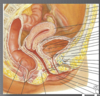

Ligament large: Décrire

- Repli de péritoine (2 feuillets accolés)

- Continuité de la séreuse de l’utérus

- Pas de fonction de support

- Traversé par l’uretère en inférieur

Ligament rond: Décrire

- Pas de franche fonction de soutien

- Départ: corne utérine

- Passe dans l’anneau inguinal

- Insertion: grande lèvre

Ligament utéro-sacré

- Principal support de l’utérus

- Contient plexus nerveux: envoie des messages de douleur

- Départ: portion postérieure du col

- Insertion: sacrum

- Inférieur au trajet de l’uretère

Ligaments cardinaux

- Ligaments de Mackenrodt

- Départ: portion latérale du col

- Insertion: paroi latérale du pelvis

- Contient les Vaisseaux utérins

- Contribue au support de l’utérus